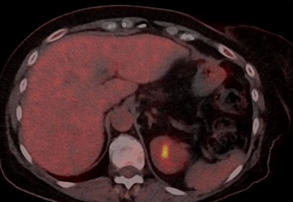

increase of dose in case of good tolerance. There were signs of a nearly

complete response of liver metastases in the control PET-CT after three months

of therapy and of complete response in the control PET-CT studies done

afterwards (Figure 2). Tolerance to TDxd has been fair, with a mild

Figure 2: Follow-up PET-CT

during the treatment with TDxd, showing complete disappearance of the liver

lesion, the other liver lesions were also disappeared